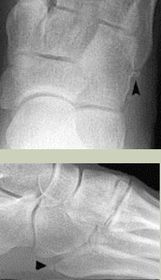

| What is this? | Calcaneonavicular coalition (AKA calcaneonavicular bar or anteater's nose) |